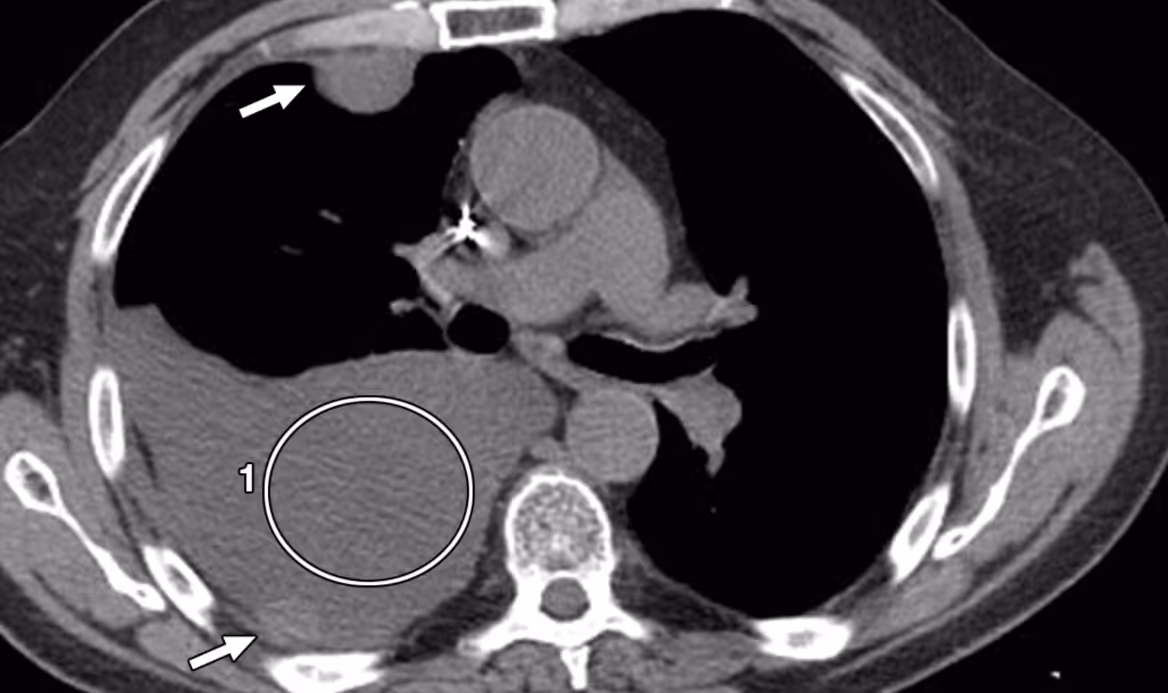

Tomografia computadorizada

A tomografia computadorizada é o exame de imagem mais completo para avaliação anatômica da cavidade pleural e estruturas adjacentes. Ele é mais indicado nos casos em que há dúvida diagnóstica, suspeita de neoplasia ou abscesso pulmonar associado, derrames loculados ou persistência do derrame mesmo após tratamento.

Nele, o líquido aparecerá como uma hipodensidade na cavidade pleural, e é possível avaliar espessamento pleural, impregnação por contraste, massas associadas, espessamento septado e presença de ar (pneumotórax ou hidropneumotórax).